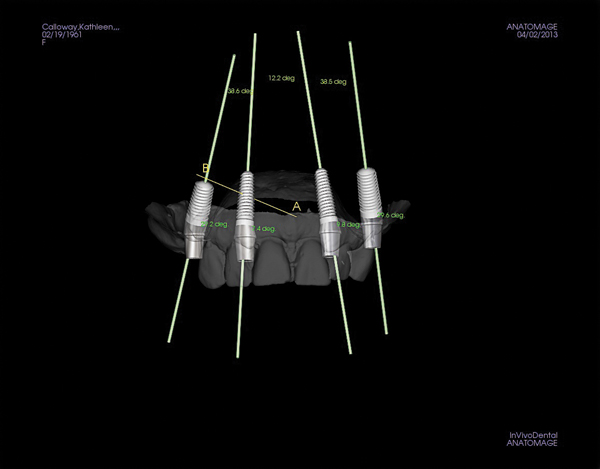

Figure 6 Implants and abutments placed, with the model turned off and the CBCT in view.

Figure 6

Figure 7 Implants and abutments in place with pinned model scan and CBCT off.

Figure 7

If the ideally designed restorations cannot be supported by available bone, additional surgical procedures, such as grafting, may be indicated. Implants can be placed in 3-D in the ideal location for esthetics and function, allowing the practitioner to visualize where osseous grafting may be needed to achieve that positioning. Alternatively, implants can be virtually positioned based on the available anatomy, respecting anatomical structures such as the inferior alveolar nerve, maxillary sinus, and the buccal/lingual plates (Figure 6 and Figure 7). This restorative-driven implant placement workflow allows general practitioners to see what may be needed to augment bone to support ideal restorations. This may alert them to the need for additional surgical procedures or to open further dialogue with surgical team members.

An additional advantage is that other members of the dental team can quickly and easily evaluate the plan via “cloud” computing or electronic transmission of the DICOM file, and once it is approved, the team can proceed using this information to create precise surgical guides that consider both hard tissue and optimal restoration location. Using both CBCT data and intraoral scan impression or model scans, the restorations can be previsualized and the implants placed accordingly.